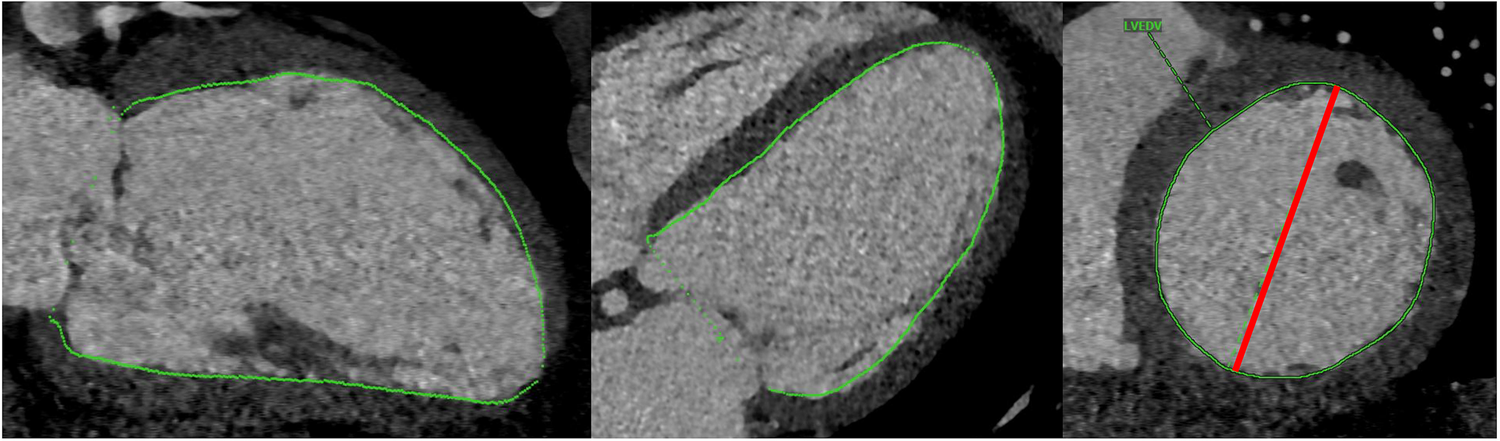

Manual CT analysis was carried out by two raters blinded to patient outcomes, one of which a board-certified cardiothoracic radiologist with 2 years of post-fellowship experience (AB) and the other a fourth-year cardiology fellow undergoing subspecialty training in multimodality cardiovascular imaging (PRe). End-systolic volume (LVESVCT) and end-diastolic volume (LVEDVCT) were derived from CT scans using commercial semi-automated 3-D segmentation software (Visage, Richmond, Australia; Figure 2). LV short axis area was manually segmented at a few locations along the ventricle and the software interpolated between the manually segmented slices. After applying slight manual corrections to the interpolated segmentation maps, LV chamber volume was calculated by taking the integral of short axis area over the length of the ventricle. Chamber segmentation maps included trabeculation and papillary muscle as part of the chamber. LV ejection fraction (LVEFCT) was calculated in the standard fashion. The maximum LV short axis diameter was recorded in end-systole and end-diastole (LVEDDCT, LVESDCT, Figure 2).

Figure 2

Depiction of chamber volume segmentation (green) and short axis diameter measurement (red).